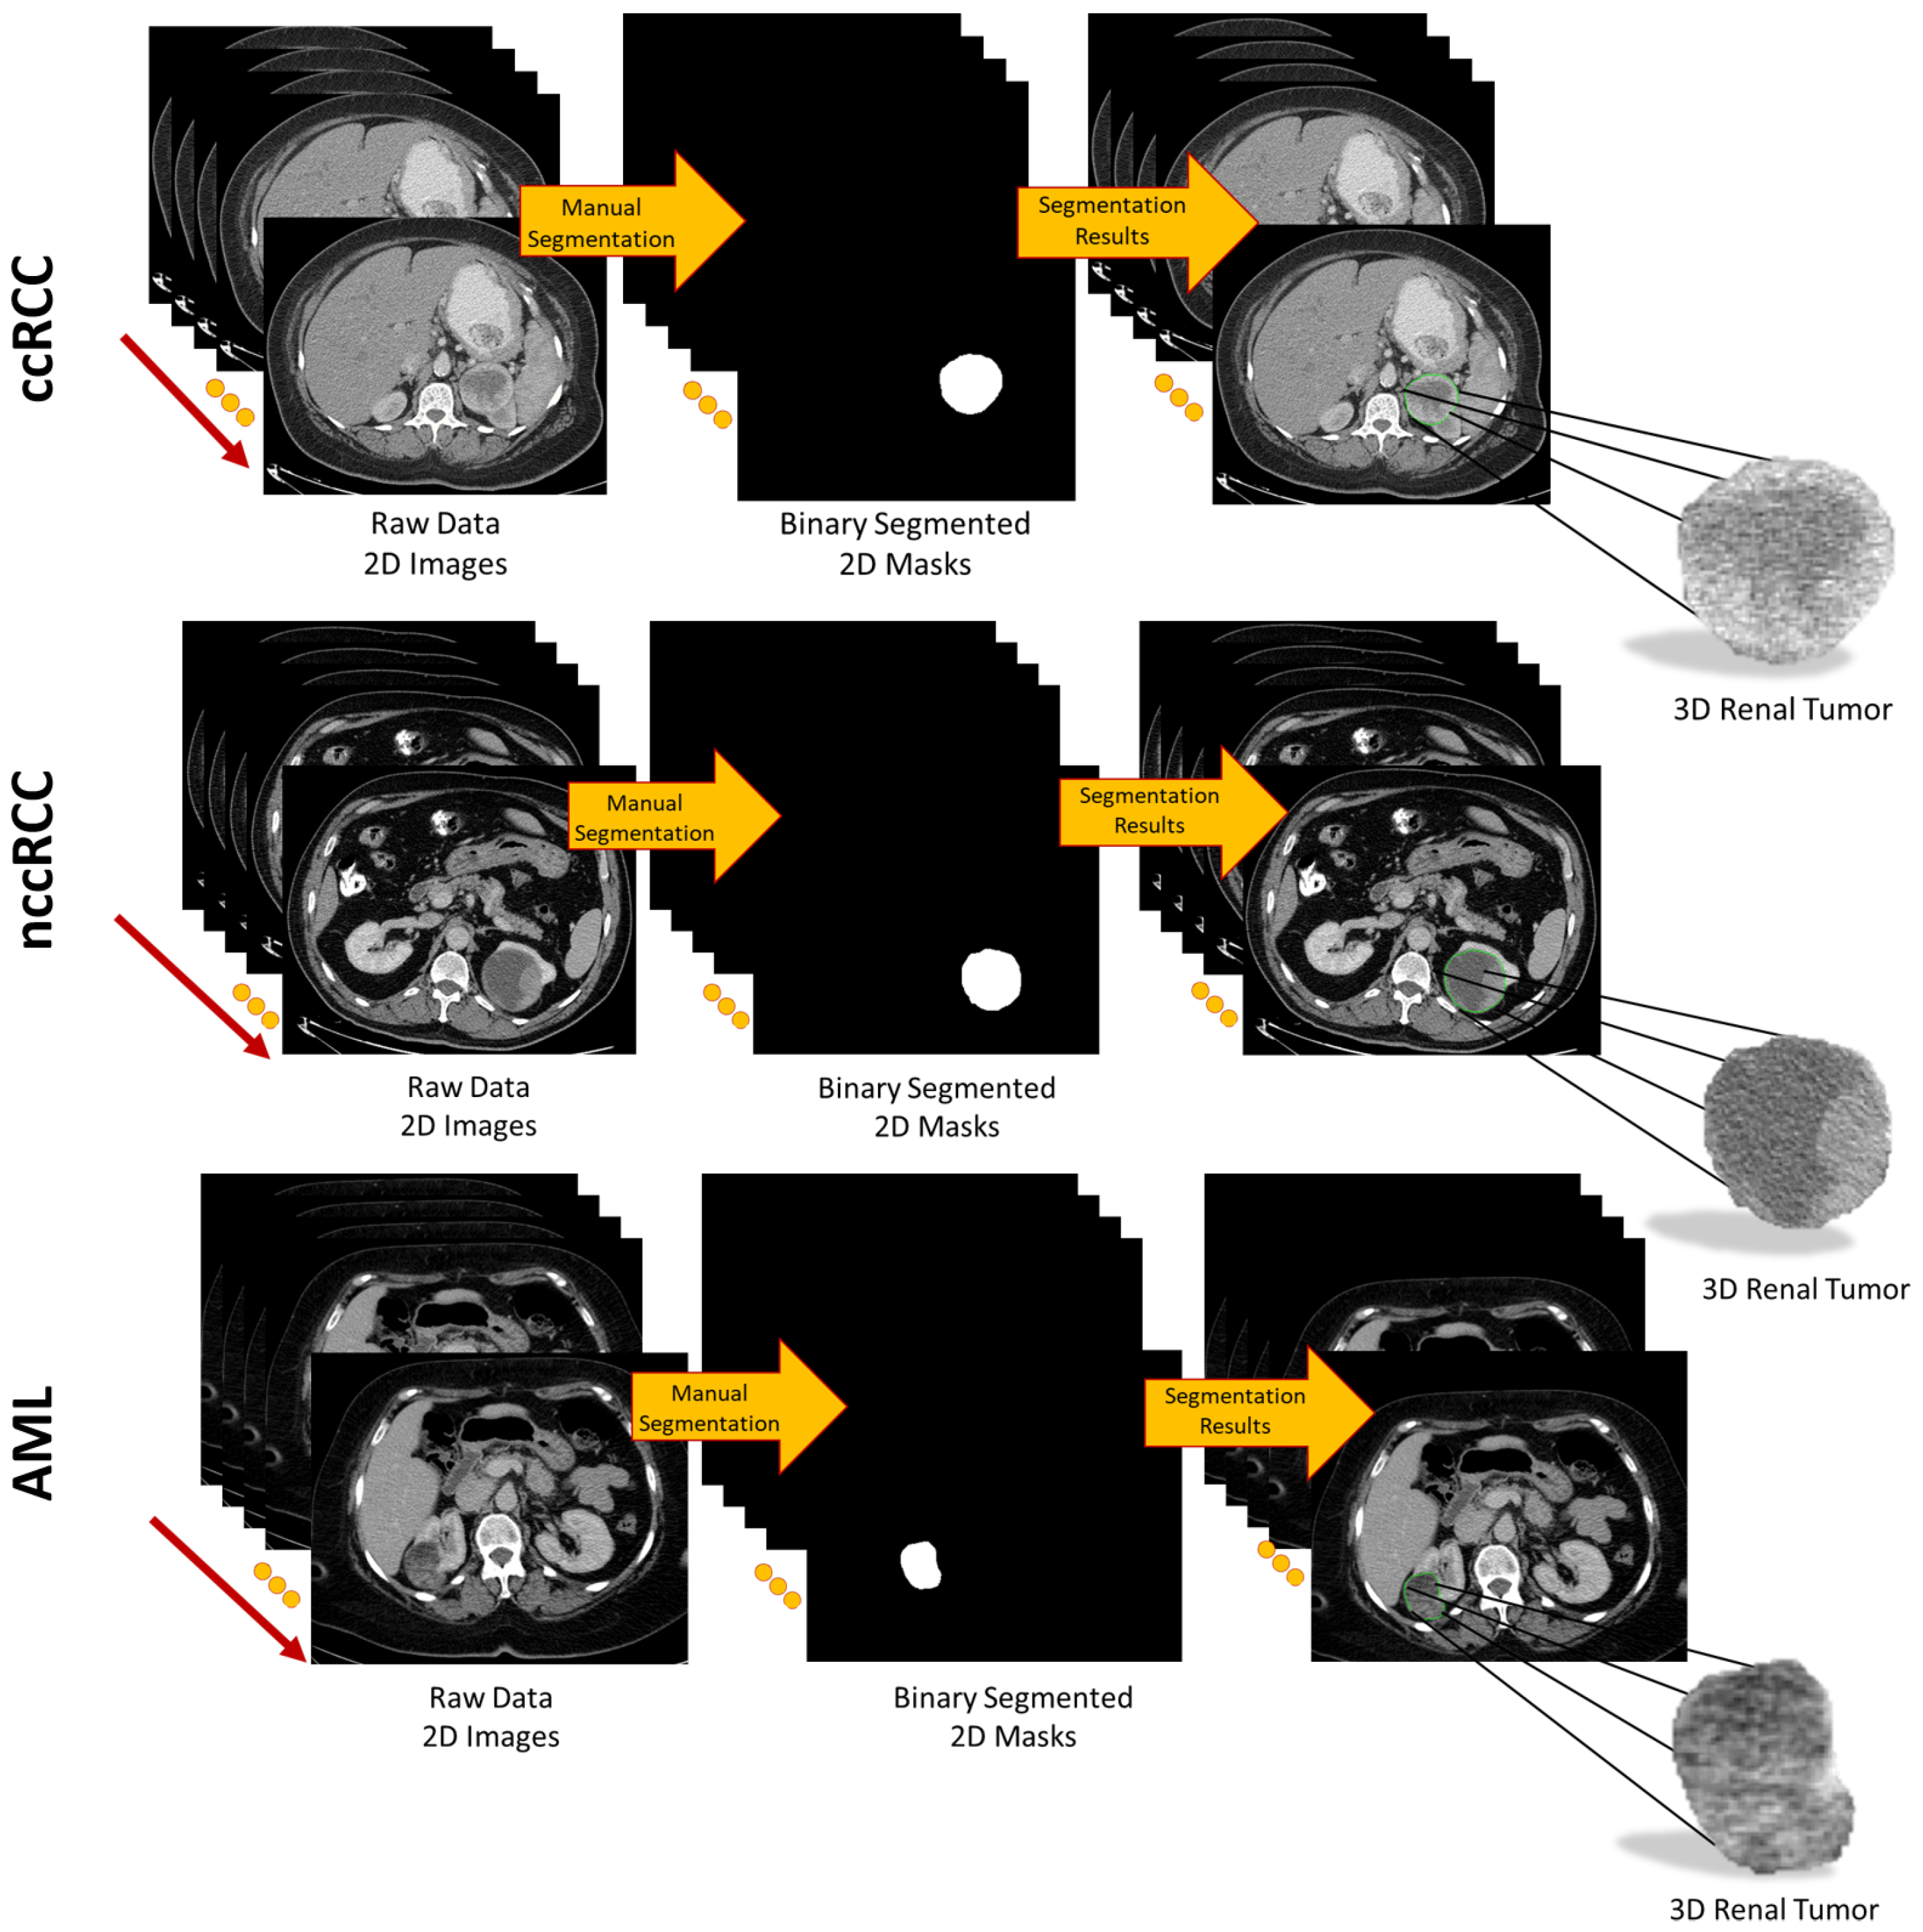

To provide a more accurate extraction of morphological, textural, and functional discriminating imaging features, for each subject, each CT slice intersecting the renal tumor was accurately and manually segmented by expert radiologists to define the 2D ROI. Then, all 2D ROIs were stacked together to construct the 3D renal tumor object (3D ROI), as shown in Figure 2.

Figure 2.

Visualization of the segmentation process to obtain 3D renal tumors.